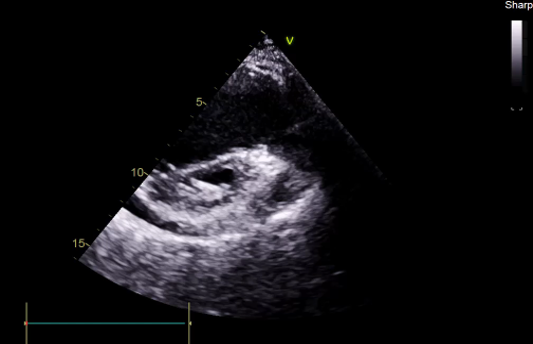

TEE, TEE and Floro showed both the leaflets to be stuck, almostno flow across the PV. The RV was higely dilated and there was severe RVdysfunction

Since TLT was not possible and surgeon refused for emergencyTranscatheter valve disruption was planned. The issues involve in the procedure were 1.Septal Puncture -due to pericardial patch in IAS, alteredanatomy due to Sx & ac dilatation of LA- Angle of puncture and Site ofpuncture. 2 Selection of wire3.Balloon- Size, make ( Compliant Vs NC), 4.Complication-like disc embolization, stuck disc leading to ac severe MA and strud fracture. The septa puncture was done as standard approach, a V18 wirewas parked in PV through a 7f Mullin sheath, Straight Turmo wire was was takenthrough a 6 JR to cross the valve and a 6 x 40 Armada balloon was dilatedacross the disc. Good acute result was obtained. The LA mean decreased from36-40 to 10-12mmHg. Post procedure the inotropic support, O2 demand decreasedover next 12 hr. However after 24 hr pt developed refractory RH failure and persistentanuria requiring SLED. And pt succumbed to the procedure 3 days after theprocedure.